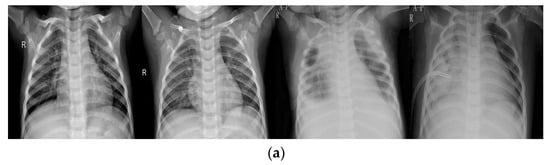

As shown in Figure 1, invalid areas in chest X-ray images make little difference to experienced radiologists or to any proposed model and would decrease classification accuracy. In order to relieve the effect of invalid areas, attention-based models were widely adopted. Li et al. [19] proposed an improved Squeeze-and-Excitation Network (SENet) architecture to locate the pneumonia area in images. Guo et al. [20] developed a model that adaptively assigned one attention score for each dense connected layer and proposed an abnormal-aware attention module to make the network weight the learned low-level features into high-level features according to the importance of features. Furthermore, they introduced a novel angular contrastive loss to reduce the loss of intra-class and enlarge the loss of inter-class. Their method achieved 89.41% accuracy in WCE images.

Figure 1.

Examples from the dataset. (a) normal cases, (b) pneumonia cases.

All images were resized to a fixed shape, which in this study is a hyper-parameter from . The training set includes a total of 4037 images, which were divided into normal and pneumonia sub-sets; the normal set contained 1093 images while the pneumonia set contained 2944 images. The validation set included a total of 579 images, which were divided into normal and pneumonia sub-sets; the normal set contained 157 images while the pneumonia set contained 422 images. The test set included a total of 1170 images; the normal set and the pneumonia set contain 316 and 854 images, respectively. Several examples of normal and pneumonia images are listed in Figure 1.